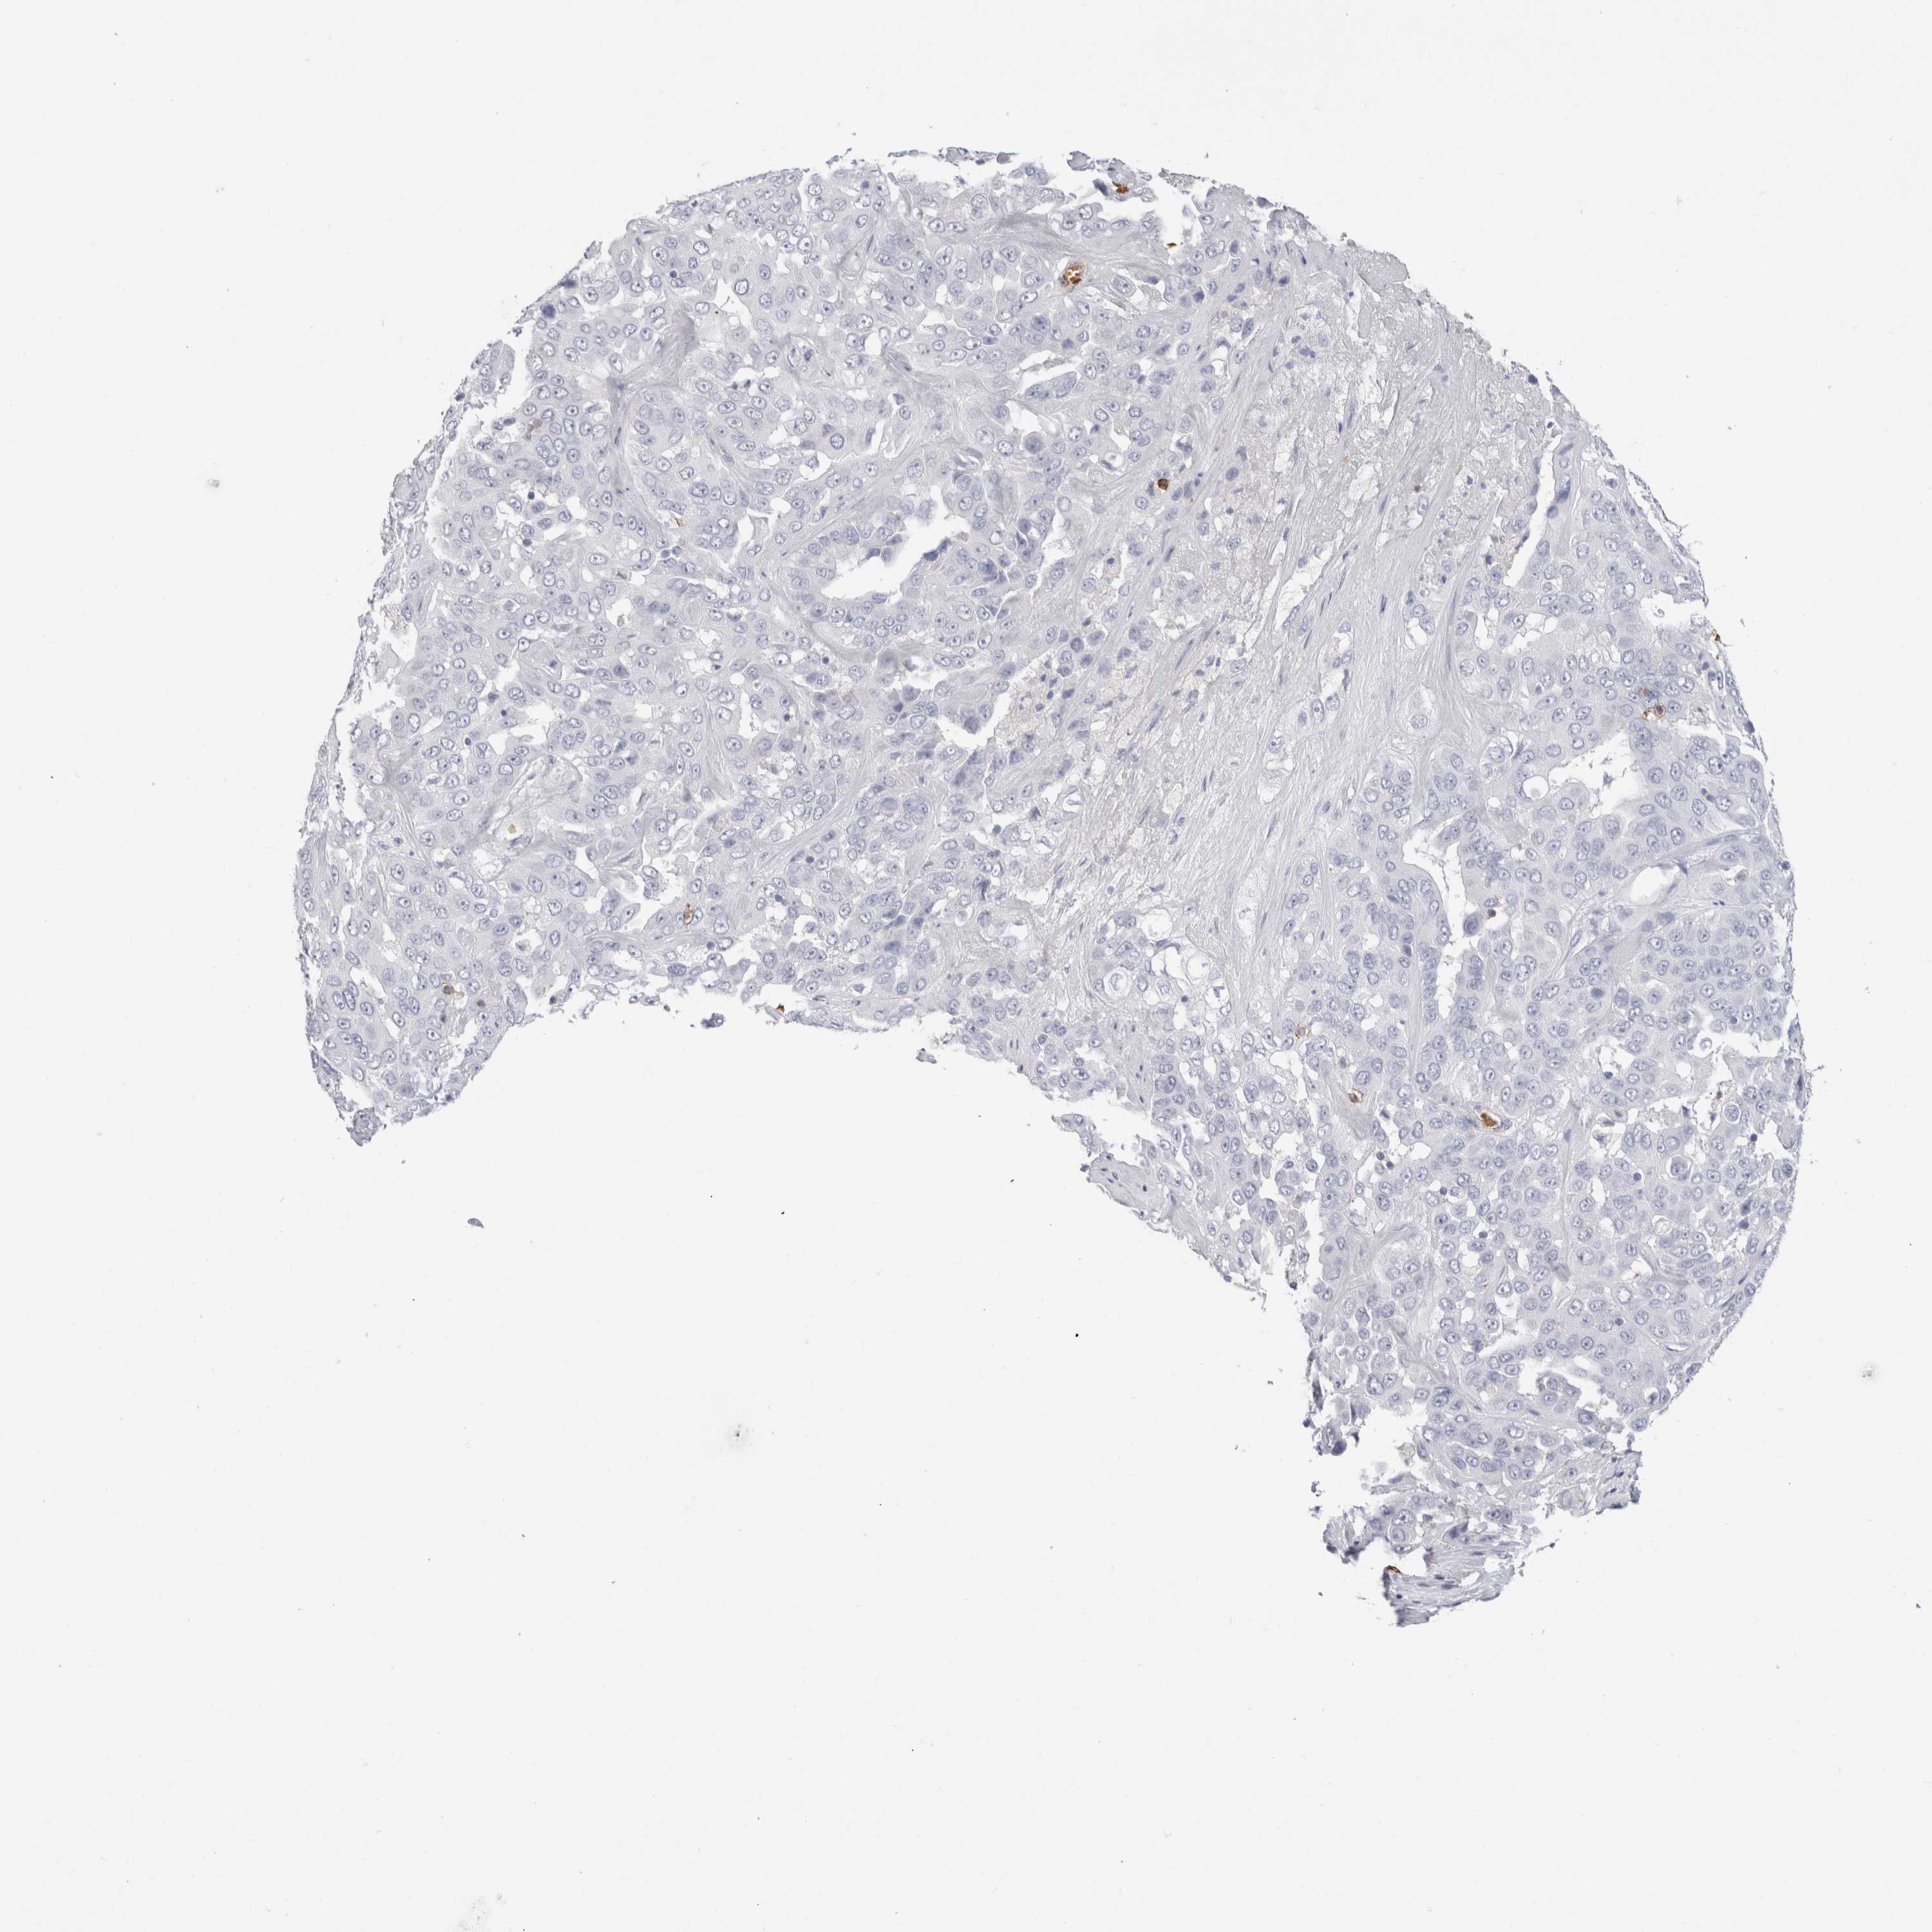

LIVER CANCER - Protein expressioni

A mouse-over function shows sample information and annotation data. Click on an image to view it in a full screen mode. Samples can be filtered based on level of antibody staining by selecting one or several of the following categories: high, medium, low and not detected. The assay and annotation is described here.

Note that samples used for immunohistochemistry by the Human Protein Atlas do not correspond to samples in the TCGA dataset.

Antibody stainingi

Antibody staining in the annotated cell types in the current human tissue is reported as not detected, low, medium, or high, based on conventional immunohistochemistry profiling in selected tissues. This score is based on the combination of the staining intensity and fraction of stained cells.

Each image is clickable and will lead to virtual microscopy that enables deeper exploration of all samples and also displays staining intensity scores, fraction scores and subcellular localization as well as patient and tissue information for each sample.

Antibody HPA022132

Antibody HPA052381

Antibody CAB002493

Antibody CAB025255

Cholangiocarcinoma

Carcinoma, Hepatocellular, NOS